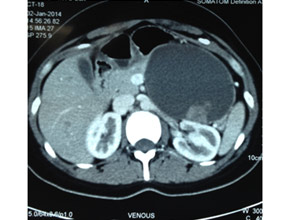

CT of pancreatic head mass showing stipled calcification

CT scan of pancreatic head mass

A continuing inflammatory process characterized by irreversible morphological change typically causing pain and loss of function. Common causes include chronic alcohol abuse, hyperlipidaemia, hypercalcaemia, malnutrition, tropical and idiopathic. Commonest mode of presentation is chronic pain (upper abdomen and back) and may be associated with Diabetes Mellitus and steatorrhoea (loose oily stools). Importantly pancreatic cancer may occur in 3%-18% of these patients. Surgery tackles pain & surrounding organ complications like duodenal and biliary obstruction secondary to a pancreatic head mass. Surgery varies from a simple pancreaticojejunostomy for Pancreatic duct drainage to the more complex head coring procedures (Frey’s and Beger’s procedure). The radical Whipple’s procedure is done when cancer cannot be ruled out.